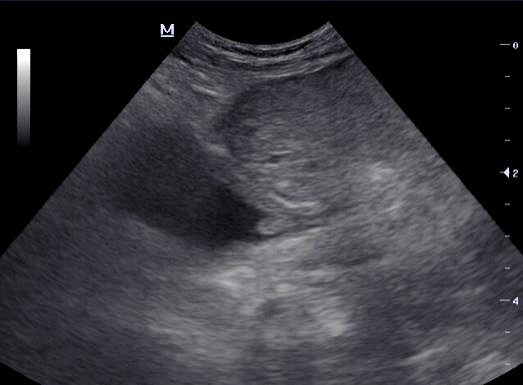

Dog and dysuric

Large mass mid-cd abdomen

What is the most likely diganosis?

Bladder neoplasia

Extra parenchymal prostatic cyst